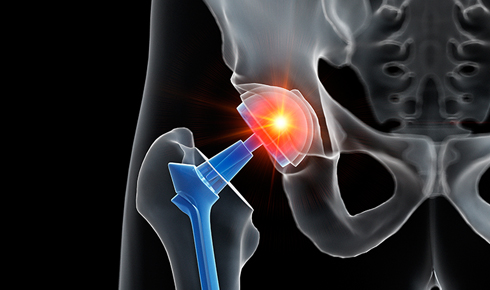

수술적 치료가 필요한 상황에서는 관절 내시경 수술이나 인공관절 치환술 등으로 기능 회복을 목표로 합니다. 치료 후에는 재발 방지와 기능 유지 차원에서 체중 관리, 올바른 자세 습관, 적절한 근력 운동을 병행하는 것이 중요합니다.